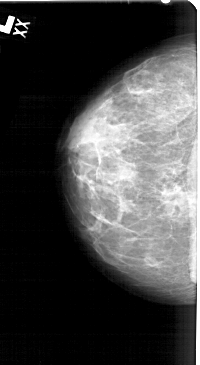

A_1546_1.RIGHT_MLO

RIGHT_MLO LINES 5491 PIXELS_PER_LINE 2941 BITS_PER_PIXEL 12 RESOLUTION 43.5 OVERLAY